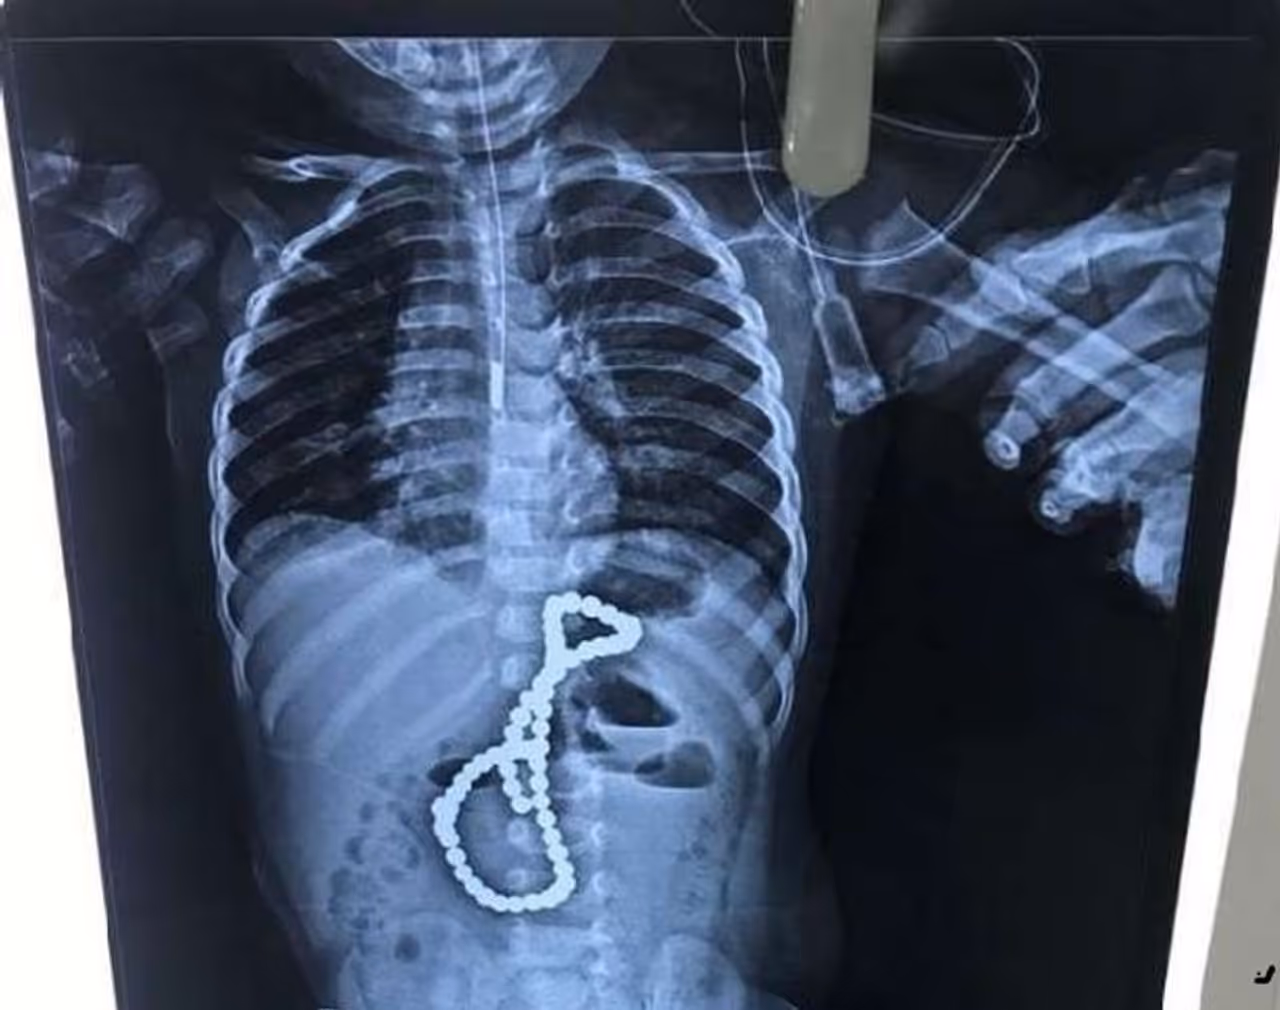

लखनऊ (Uttar Pradesh) । डेढ़ साल का का एक बच्चा खेल-खेल में चुंबकनुमा 65 मोतियों वाली माला निगल गया। हैरानी की बात यह कि परिवार के लोगों को इसकी जानकारी नहीं हो सकी, जबकि बच्चा लगातार उल्टियां कर रहा था और रो रहा था। बावजूद इसके उसे अस्पताल नहीं ले गए। जब बच्चे की हालत काफी गंभीर हो गई तो पांचवें दिन उसे एक निजी चिकित्सक के पास ले गए। जहां हालत नाजुक देख एक्सरे कराया गया, जिसकी रिपोर्ट देखकर सभी हैरान हो गए।

चार दिन तक आराम नहीं होने पर परिवार के लोग पांचवें दिन बच्चे को लेकर गोमती नगर स्थित एक निजी अस्पताल पहुंचे थे। जहां पर उसे डिहाइड्रेशन की शिकायत के चलते भर्ती किया गया। परिवार के लोग बच्चे की तबीयत खराब होने के पीछे कोई सटीक हिस्ट्री नहीं बता सके। डॉ. सुनील कन्नौजिया के अनुसार एक्सरे करने पर उसके पेट में माला नजर आई। तब भी परिवारजन को भरोसा नहीं हुआ। अभिभावक घर में किसी भी तरह की माला न होने की बात बताने लगे।

पेट में चीरा लगाने के दौरान उपकरण उसमें चिपकने लगे, जिससे पता चला की माला चुंबकयुक्त है। इसके बाद डॉक्टरों ने लोहे के उपकरण का सहारा लिया। आंत में चुंबक के मोती आपस में चिपक गए थे। इससे आंतों की चाल भी गड़बड़ा गई और उसमें कई सुराख हो गए। ये मोती छोटी और बड़ी आंत दोनों में पहुंच गए थे। इससे छोटी आंत में पांच और पेट के पीछे हिस्से में एक सुराख हो गया था।